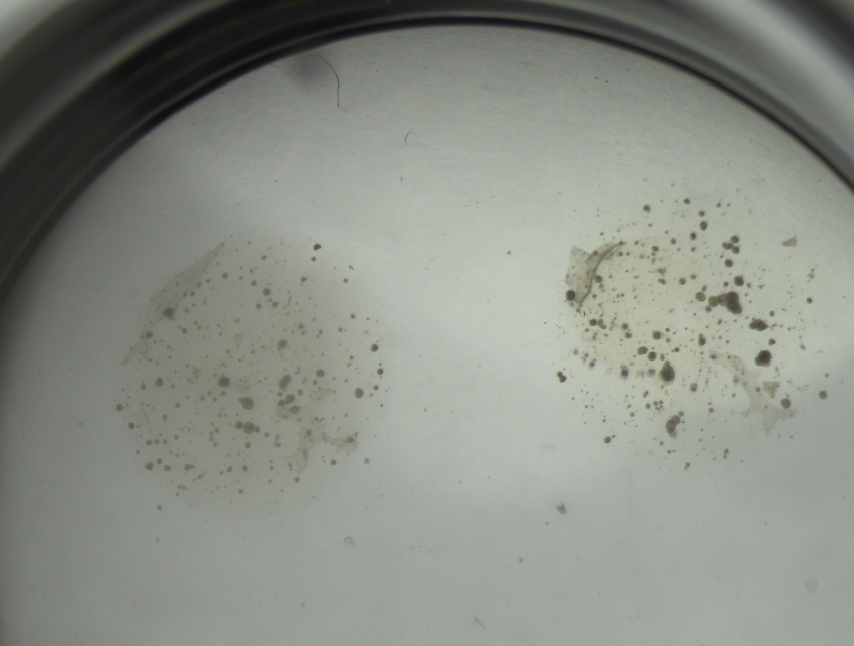

Implanting cells into hydrogel and performing live/dead stain assay.

Bioreactor grown canine organoids.